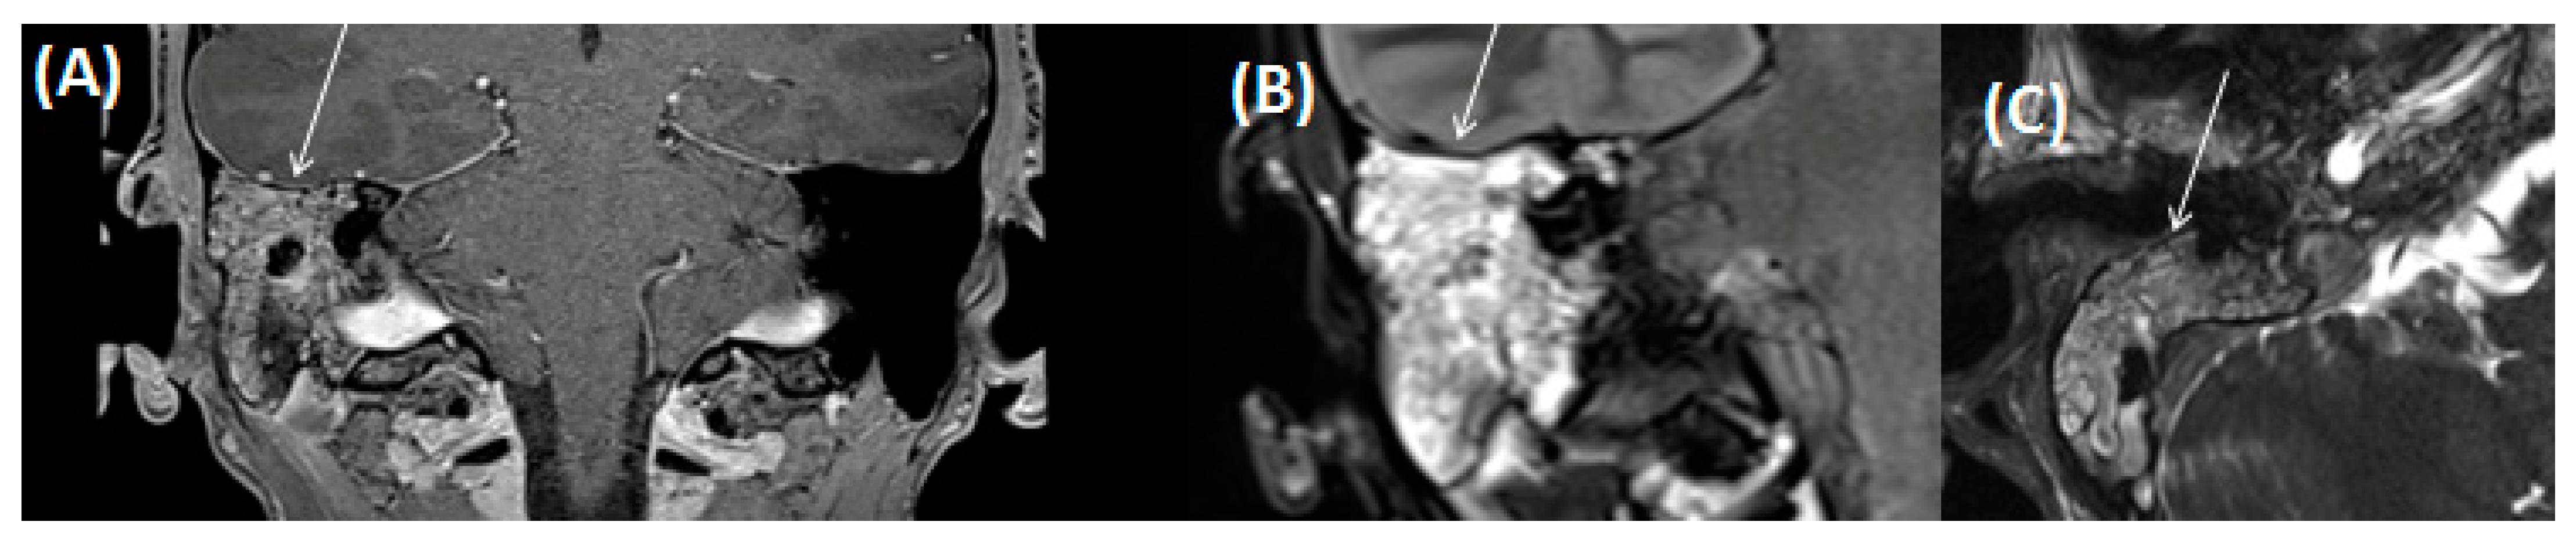

3.2.5. Cholesterol Granuloma